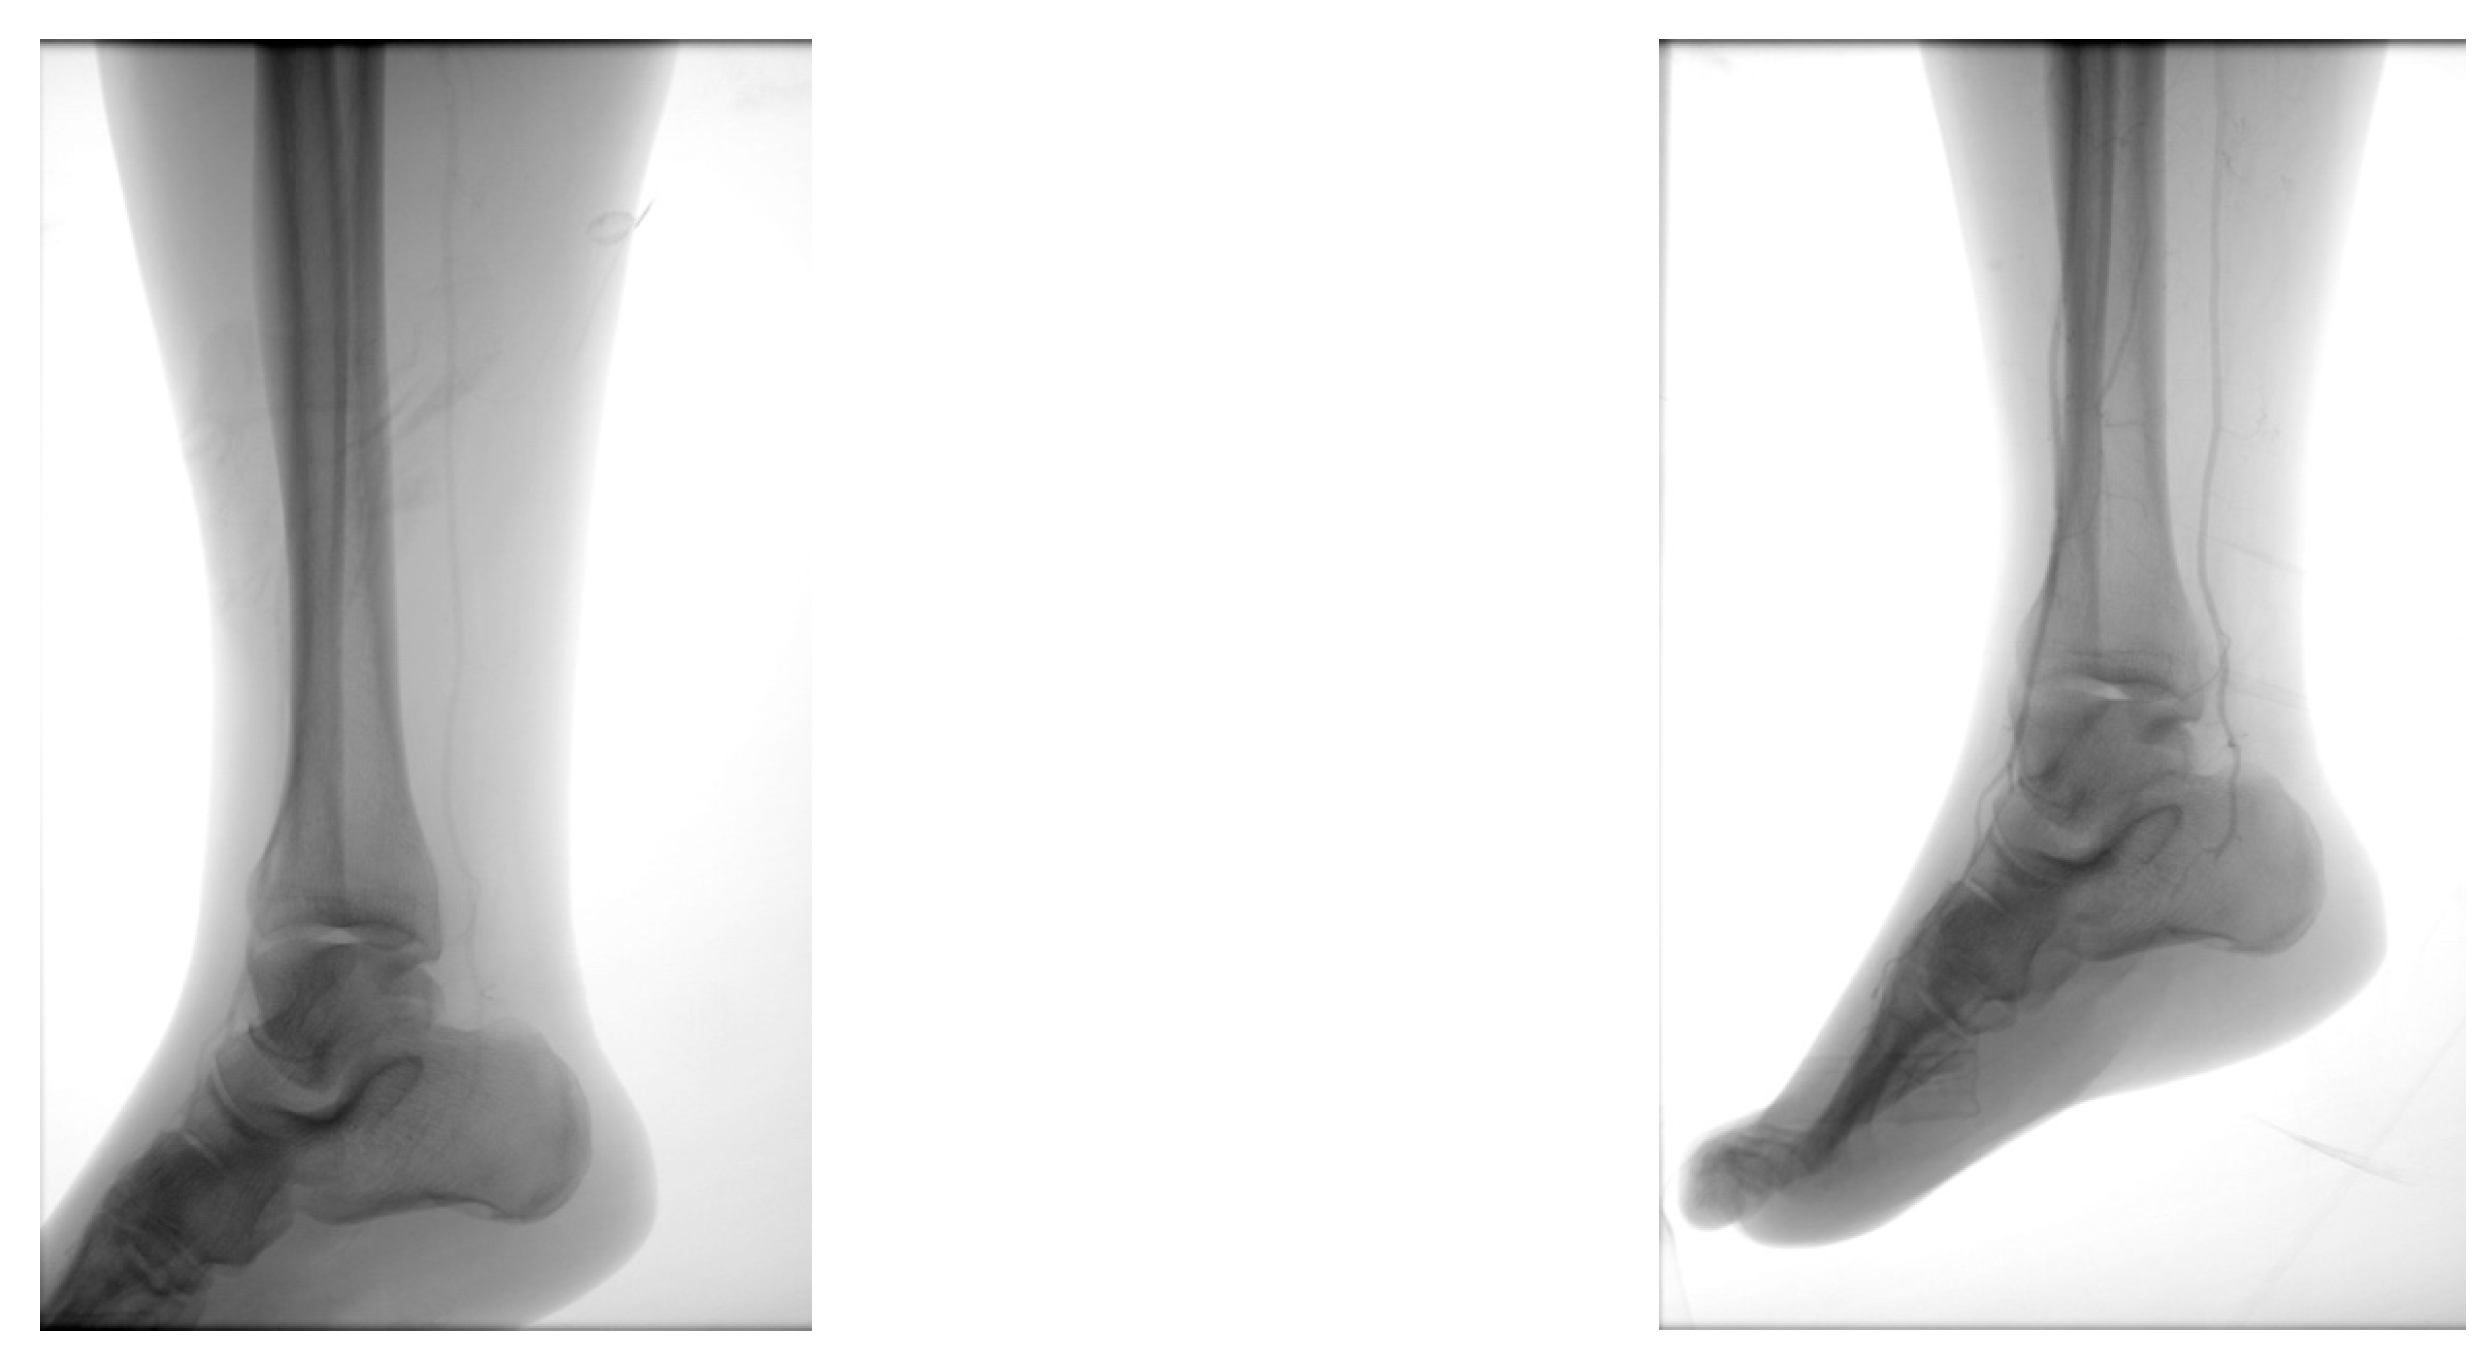

4.1. Case 1—Direct Revascularization-Minor Amputation

4.2. Case 2—Indirect Revascularization-Major Amputation